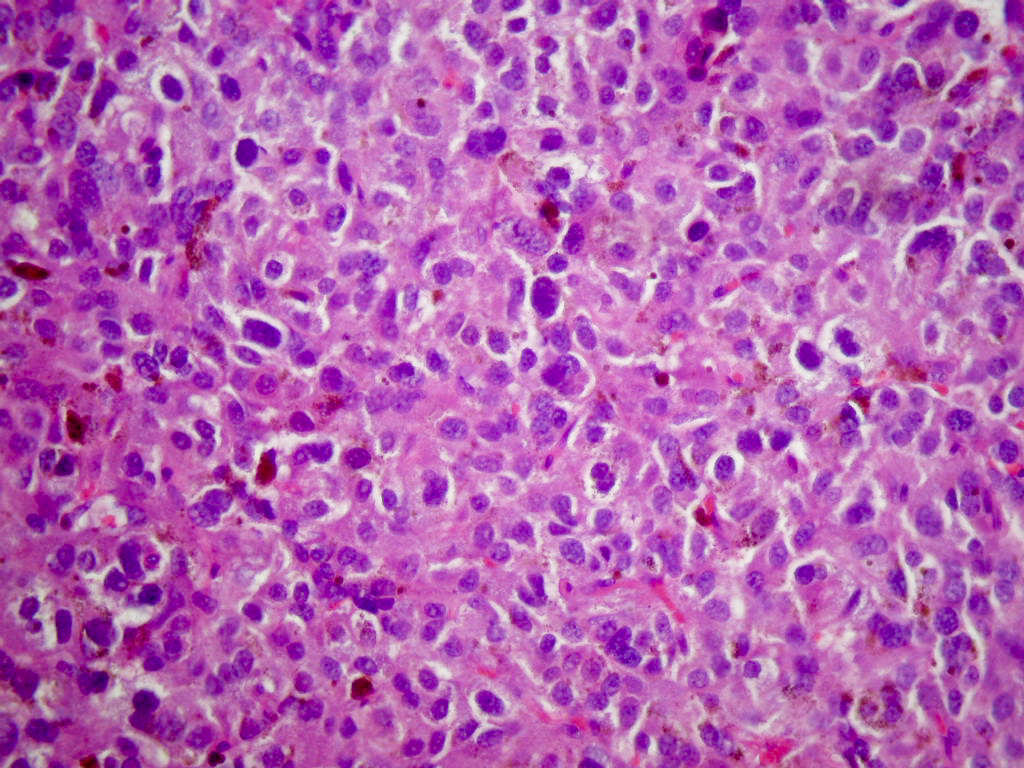

- Classic histologic morphology: monomorphic cells with abundant eosinophilic / amphophilic cytoplasm arranged in a nested / zellballen pattern and separated by fibrovascular septa with sustentacular cells

Microscopic (histologic) description

- Typical morphology: epithelioid cells with abundant, eosinophilic / amphophilic, granular cytoplasm and round / ovoid, vesicular / salt and pepper nuclei, arranged in a nested / zellballen pattern and separated by fibrovascular septae with sustentacular cells (Am J Surg Pathol 2004;28:94, World J Clin Cases 2014;2:591, Endocr Pathol 2022;33:90)

- May have focal pleomorphism, nuclear hyperchromasia, low mitotic activity or clear cytoplasm

Microscopic (histologic) images

Contributed by Theodorus H. van der Kwast, M.D., Ph.D., Michelle R. Downes, M.D., Debra L. Zynger, M.D. and David Cohen, M.B.B.Ch., M.D.

- Tumor cells arranged in clusters or singly (Diagn Cytopathol 2017;45:350)

- Epithelioid cells with abundant, finely granular, pale cytoplasm

- Ovoid nuclei with smooth contour, fine chromatin and inconspicuous nucleoli

- Occasional spindle sustentacular cells admixed within clusters of tumor cells

- Naked nuclei present

- Microscopic description: This specimen shows an unencapsulated, monomorphous population of round tumor cells in a nested / zellballen pattern with delicate vascular septa and intervening extravasated red blood cells. It predominantly involves the lamina propria of the bladder but in 1 tissue piece clearly involves muscularis propria. The tumor cells have abundant amphophilic cytoplasm and vesicular chromatin with occasional small nucleoli. There is no necrosis, diffuse growth pattern or vascular space invasion identified. The mitotic count is (maximally) 1/10 high power fields. Immunohistochemistry shows the tumor cells to be positive for GATA3 with strong and diffuse expression of synaptophysin and chromogranin, as well as retention of SDHB staining. The tumor cells are negative for AE1 / AE3, HMWK and p63. The Ki67 proliferation index is < 1%. S100 shows faint nuclear and cytoplasmic staining with occasional sustentacular cells identified.

- Microscopic description: Sections show unremarkable surface urothelium with a lesion in the deep lamina propria comprised of large eosinophilic cells with hyperchromatic, focally enlarged nuclei with occasional intranuclear inclusions. A fine vascular plexus is identified in some areas. Necrosis and hemorrhage are not identified. Mitotic rate = 1/10 high power fields (field of view [FOV] = 0.55 mm). The lesion extends to the cauterized base of the specimen. Immunostains confirm the lesion expresses synaptophysin, chromogranin and GATA3. SDHB is retained. AE1 / AE3, CD45, p63 and NKX3.1 are negative.